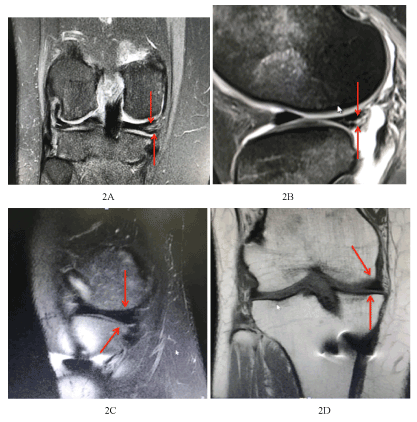

Figure 2. 42-year-old, MRI of Right Knee, Coronal section medial meniscus shows intra-meniscal increased signal intensity suggesting tear reaching the most medial outer surface and inferior articular with associate joint effusion. 42-year-old, post ACL reconstruction, MRI of Right Knee, Coronal section and sagittal views showing healed Medial meniscus